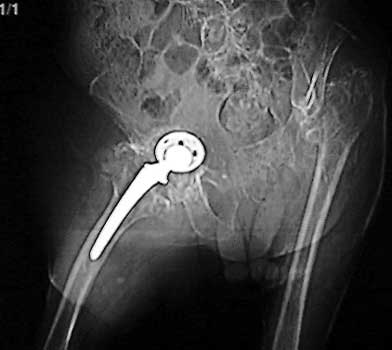

INFECTION—Soft tissue gas.

Gas in neo capsule of right total hip replacement secondary to sinus tract from joint to skin

INFECTION—Soft tissue gas adjacent to dislocated cement spacer

INFECTION—Gas bubbles in synovial cyst anterior to right total hip replacement. Patient had infected left hip joint 1 year previously treated by Girdlestone procedure. Right total hip replacement was grossly loose and with migrated hardware.